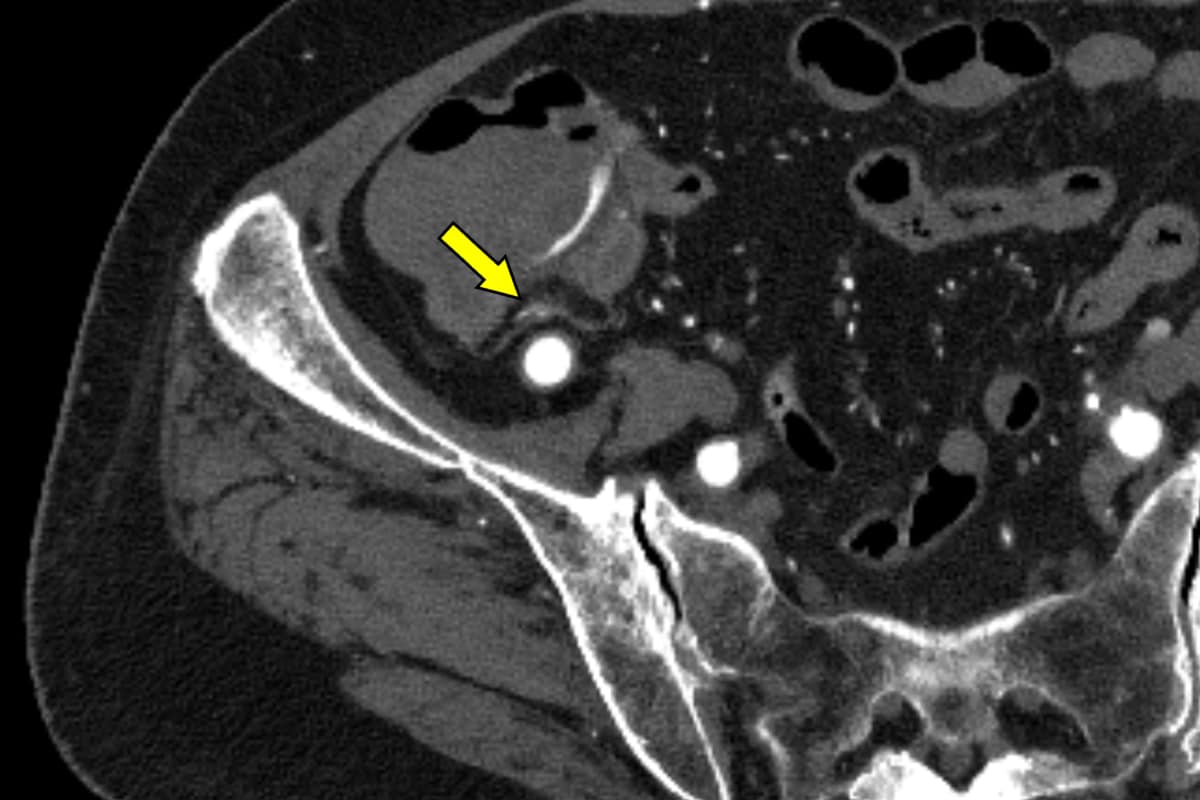

血便があり、当院消化器内科に入院となった。第3病日に下部消化管内視鏡を行うも出血源は不明であった。第4病日に再度血便があり、造影CTを施行すると上行結腸憩室からの活動性出血を認めたため、速やかに緊急TAEを施行した。血管造影で回結腸動脈の分枝からextravasationを認め、責任動脈をコイル塞栓した。術後、再出血、Hb値の低下を認めず、第13病日に退院となった。

消化管出血では出血源を迅速かつ正確に同定することが診療上、不可欠である。内視鏡は有用であるものの、腸管の前処置を要し、観察に時間を要する他、出血が間欠的であれば診断が困難となる場合がある。これに対して造影CTは、非侵襲的かつ短時間で活動性出血の有無と局在を明確に描出できる。活動性出血があれば、動脈相から腸管内への造影剤の漏出を認め、静脈相や遅延相ではその造影剤漏出の拡大を確認することで、客観的に活動性出血を診断できる。さらに、造影CTで得られた情報に基づき責任血管を同定することで、後続の血管造影検査の効率が高まり、速やかに経カテーテル的動脈塞栓術(TAE)へと移行できる。当院では、造影CTで活動性出血が確認された結腸憩室出血に対して速やかにTAEを施行しており、その成功率向上に寄与している。一方で、出血が間欠的または少量の場合には描出が難しく、検査のタイミングによって診断能が左右されるという限界もある。それでも、結腸憩室出血において造影CTは診断と治療方針をつなぐ、重要な検査として位置付けられる。

本症例ではPhoton Counting CT(PCCT)を用いた。PCCTは従来型CTに比べ空間分解能とコントラスト分解能が高く、少量の造影剤でも高精細な画像を得られることが特徴である。これにより微細なextravasationやそれに連続する責任動脈の描出が可能となり、診断精度を大きく高める。

PCCTによる高精細な画像はextravasationの検出にとどまらず、責任血管を描出することで標的血管の特定を容易にする。その結果、血管造影での探索時間が短縮され、経カテーテル動脈塞栓術(TAE)の迅速かつ確実な施行につながり、手技の成功率と効率を高めている。